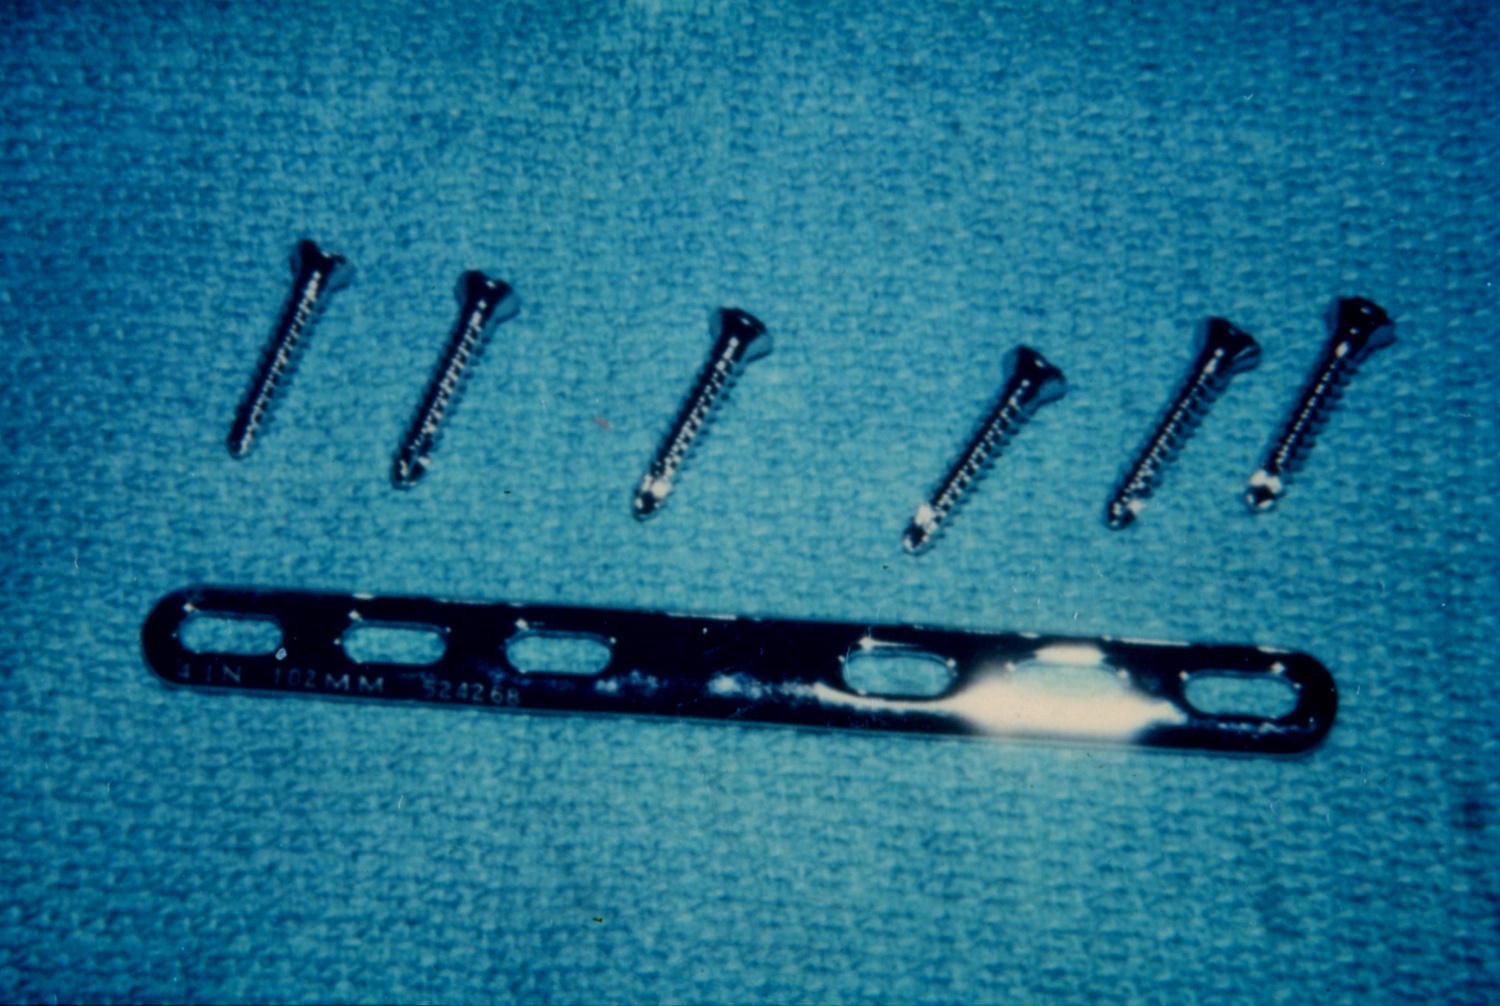

- Volar plate fixation

- Most common surgical approach

- Fixation may be more difficult when the fracture is in the distal third of the radius, where it may only be possible to insert two screws distal to the fracture line in these cases if using a 3.5-mm straight plate.1 Modern T-plates provide better fixation in the distal fragment by allowing additional screws in the distal fragment.